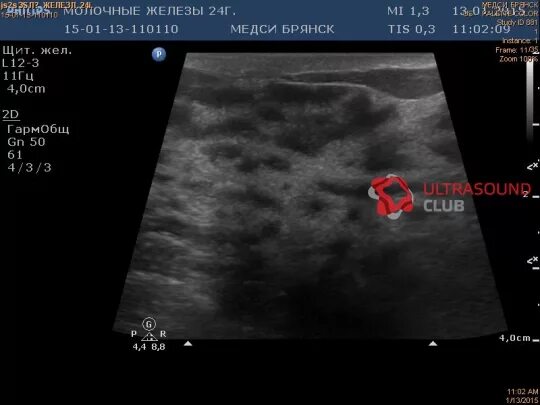

Диффузные фиброзные изменения молочной железы